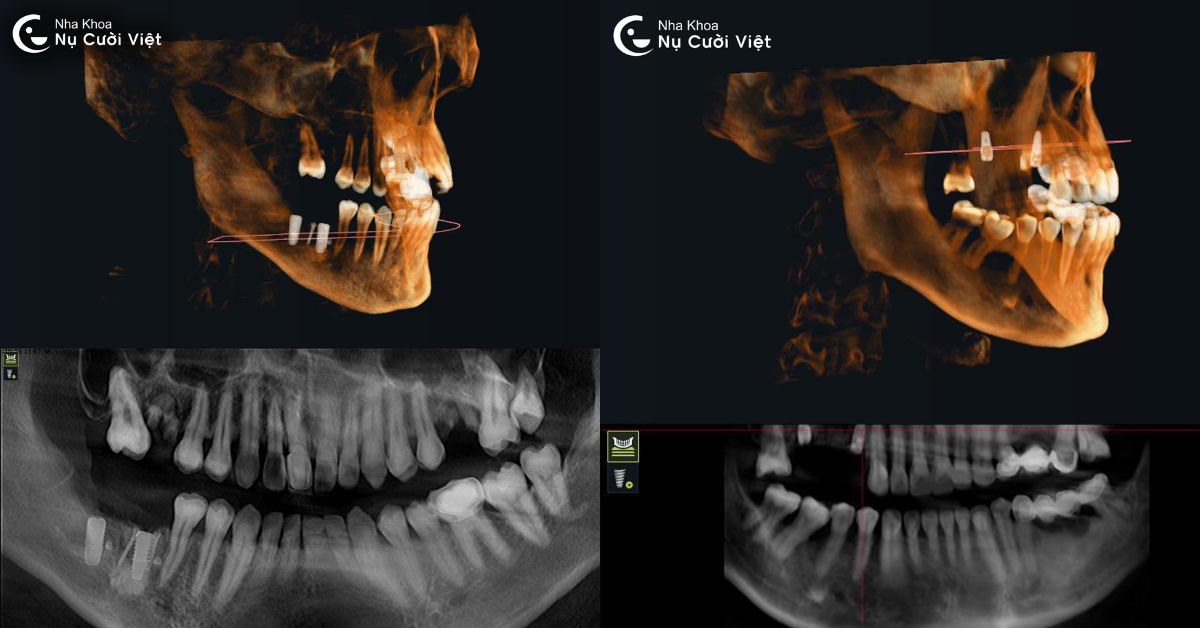

Chính vì vậy, chụp phim ConeBeam CT 3D là bước đầu tiên và không thể thiếu trong quá trình trồng răng Implant. Công nghệ này không chỉ giúp bác sĩ quan sát toàn diện vùng hàm mặt mà còn tạo nền tảng dữ liệu 3D chính xác, phục vụ cho việc lập kế hoạch điều trị an toàn, cá nhân hóa cho từng bệnh nhân.

Kỹ thuật này sử dụng tia X hình nón để quét toàn bộ cấu trúc vùng hàm mặt và răng trong một lần chụp duy nhất. So với phim X-quang thông thường chỉ cho hình ảnh hai chiều (2D), ConeBeam CT cung cấp góc nhìn toàn cảnh ba chiều (3D) có độ phân giải cao, thể hiện chi tiết từng lát cắt của xương, mô mềm, ống thần kinh và xoang hàm. Khi thực hiện chụp, đầu máy sẽ xoay 360 độ quanh vùng hàm mặt trong vài giây để thu thập dữ liệu. Hệ thống cảm biến đặc biệt sẽ ghi lại hàng trăm lớp cắt siêu mỏng của vùng cần khảo sát.

Chỉ với một lần chụp duy nhất, bác sĩ có thể quan sát hàng triệu góc nhìn, từ trên xuống, từ dưới lên, mặt bên, mặt nghiêng… Từ đó dễ dàng phát hiện các vấn đề tiềm ẩn như tiêu xương, viêm quanh chân răng cũ, khoảng cách đến dây thần kinh, độ sâu xoang hàm… giúp quá trình lập kế hoạch trồng Implant trở nên chính xác và cá nhân hóa cho từng khách hàng.

Cone Beam CT tạo ra hình ảnh 3D chi tiết giúp đánh giá chính xác cấu trúc xương, tình trạng mô mềm